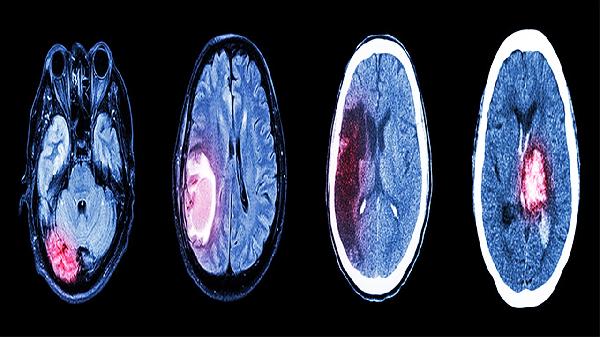

脑得生片可用于治疗脑动脉硬化。脑动脉硬化可能由长期高血压、高脂血症等因素引起,通常表现为头晕、记忆力减退、注意力不集中等症状。脑得生片中的三七有助于扩张血管、改善脑部供血,红花可抑制血小板聚集,减少血栓形成风险。用药期间宜低盐低脂饮食,避免情绪激动。若出现视物模糊或肢体麻木加重,需及时复查CT或MRI。

脑得生片适用于缺血性脑卒中后的功能障碍恢复。此类后遗症多因脑血管阻塞导致脑组织缺血损伤,常见症状包括言语不清、偏侧肢体无力等。药物中的葛根素能提高脑细胞耐缺氧能力,红花提取物可促进侧支循环建立。康复期间需配合肢体功能训练,定期监测凝血功能,避免与抗凝药物联用增加出血风险。

脑得生片对脑出血后遗留的 neurological deficits 有一定改善作用。脑出血后局部淤血可能压迫神经组织,引发运动障碍或感觉异常。该药通过活血成分加速血肿吸收,但需在出血稳定后2-4周才开始使用,切忌急性期服用。用药期间需严格控制血压,若出现恶心呕吐或意识变化应立即停药并复查头颅CT。